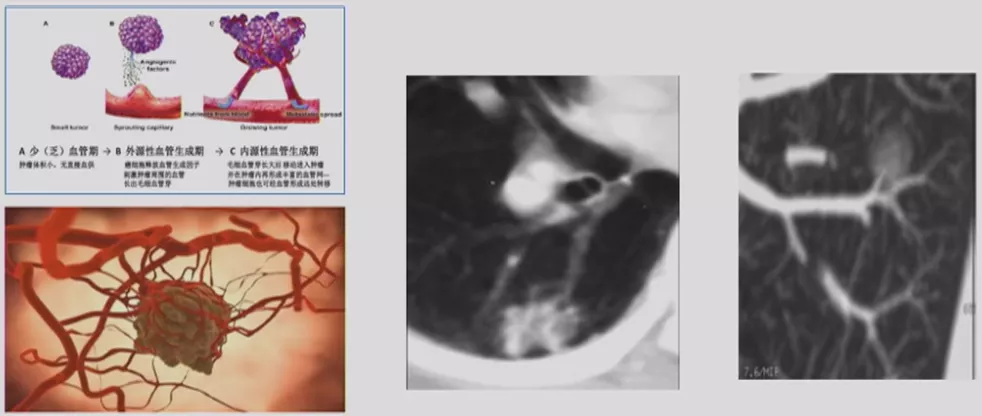

微小结节影像特征

国内、国外都有学者做微小结节相关的研究,以上是张国桢教授的书中所描述的征象。肿瘤的生长需要血管,没有供血的话无法生长。肿瘤的供血很丰富,里面血管很紊乱。这个时候如果我们用现代增强CT扫描,用薄层CT、三维重建,可以看到滋养血管进入肿瘤,我们叫做肿瘤微血管移动征。如果「肿瘤血管」增生形成杂乱新生的毛细血管网,我们叫做联通征。这有助于肺癌的早期诊断。

微小结节的影像特征——周围血管特征

现在有数字肺软件等多种技术,可以对血管进行定量的分析,显示出立体结构,观察结节有多少个血管、进去的角度怎么样、指向如何等等,这些都非常有意义。